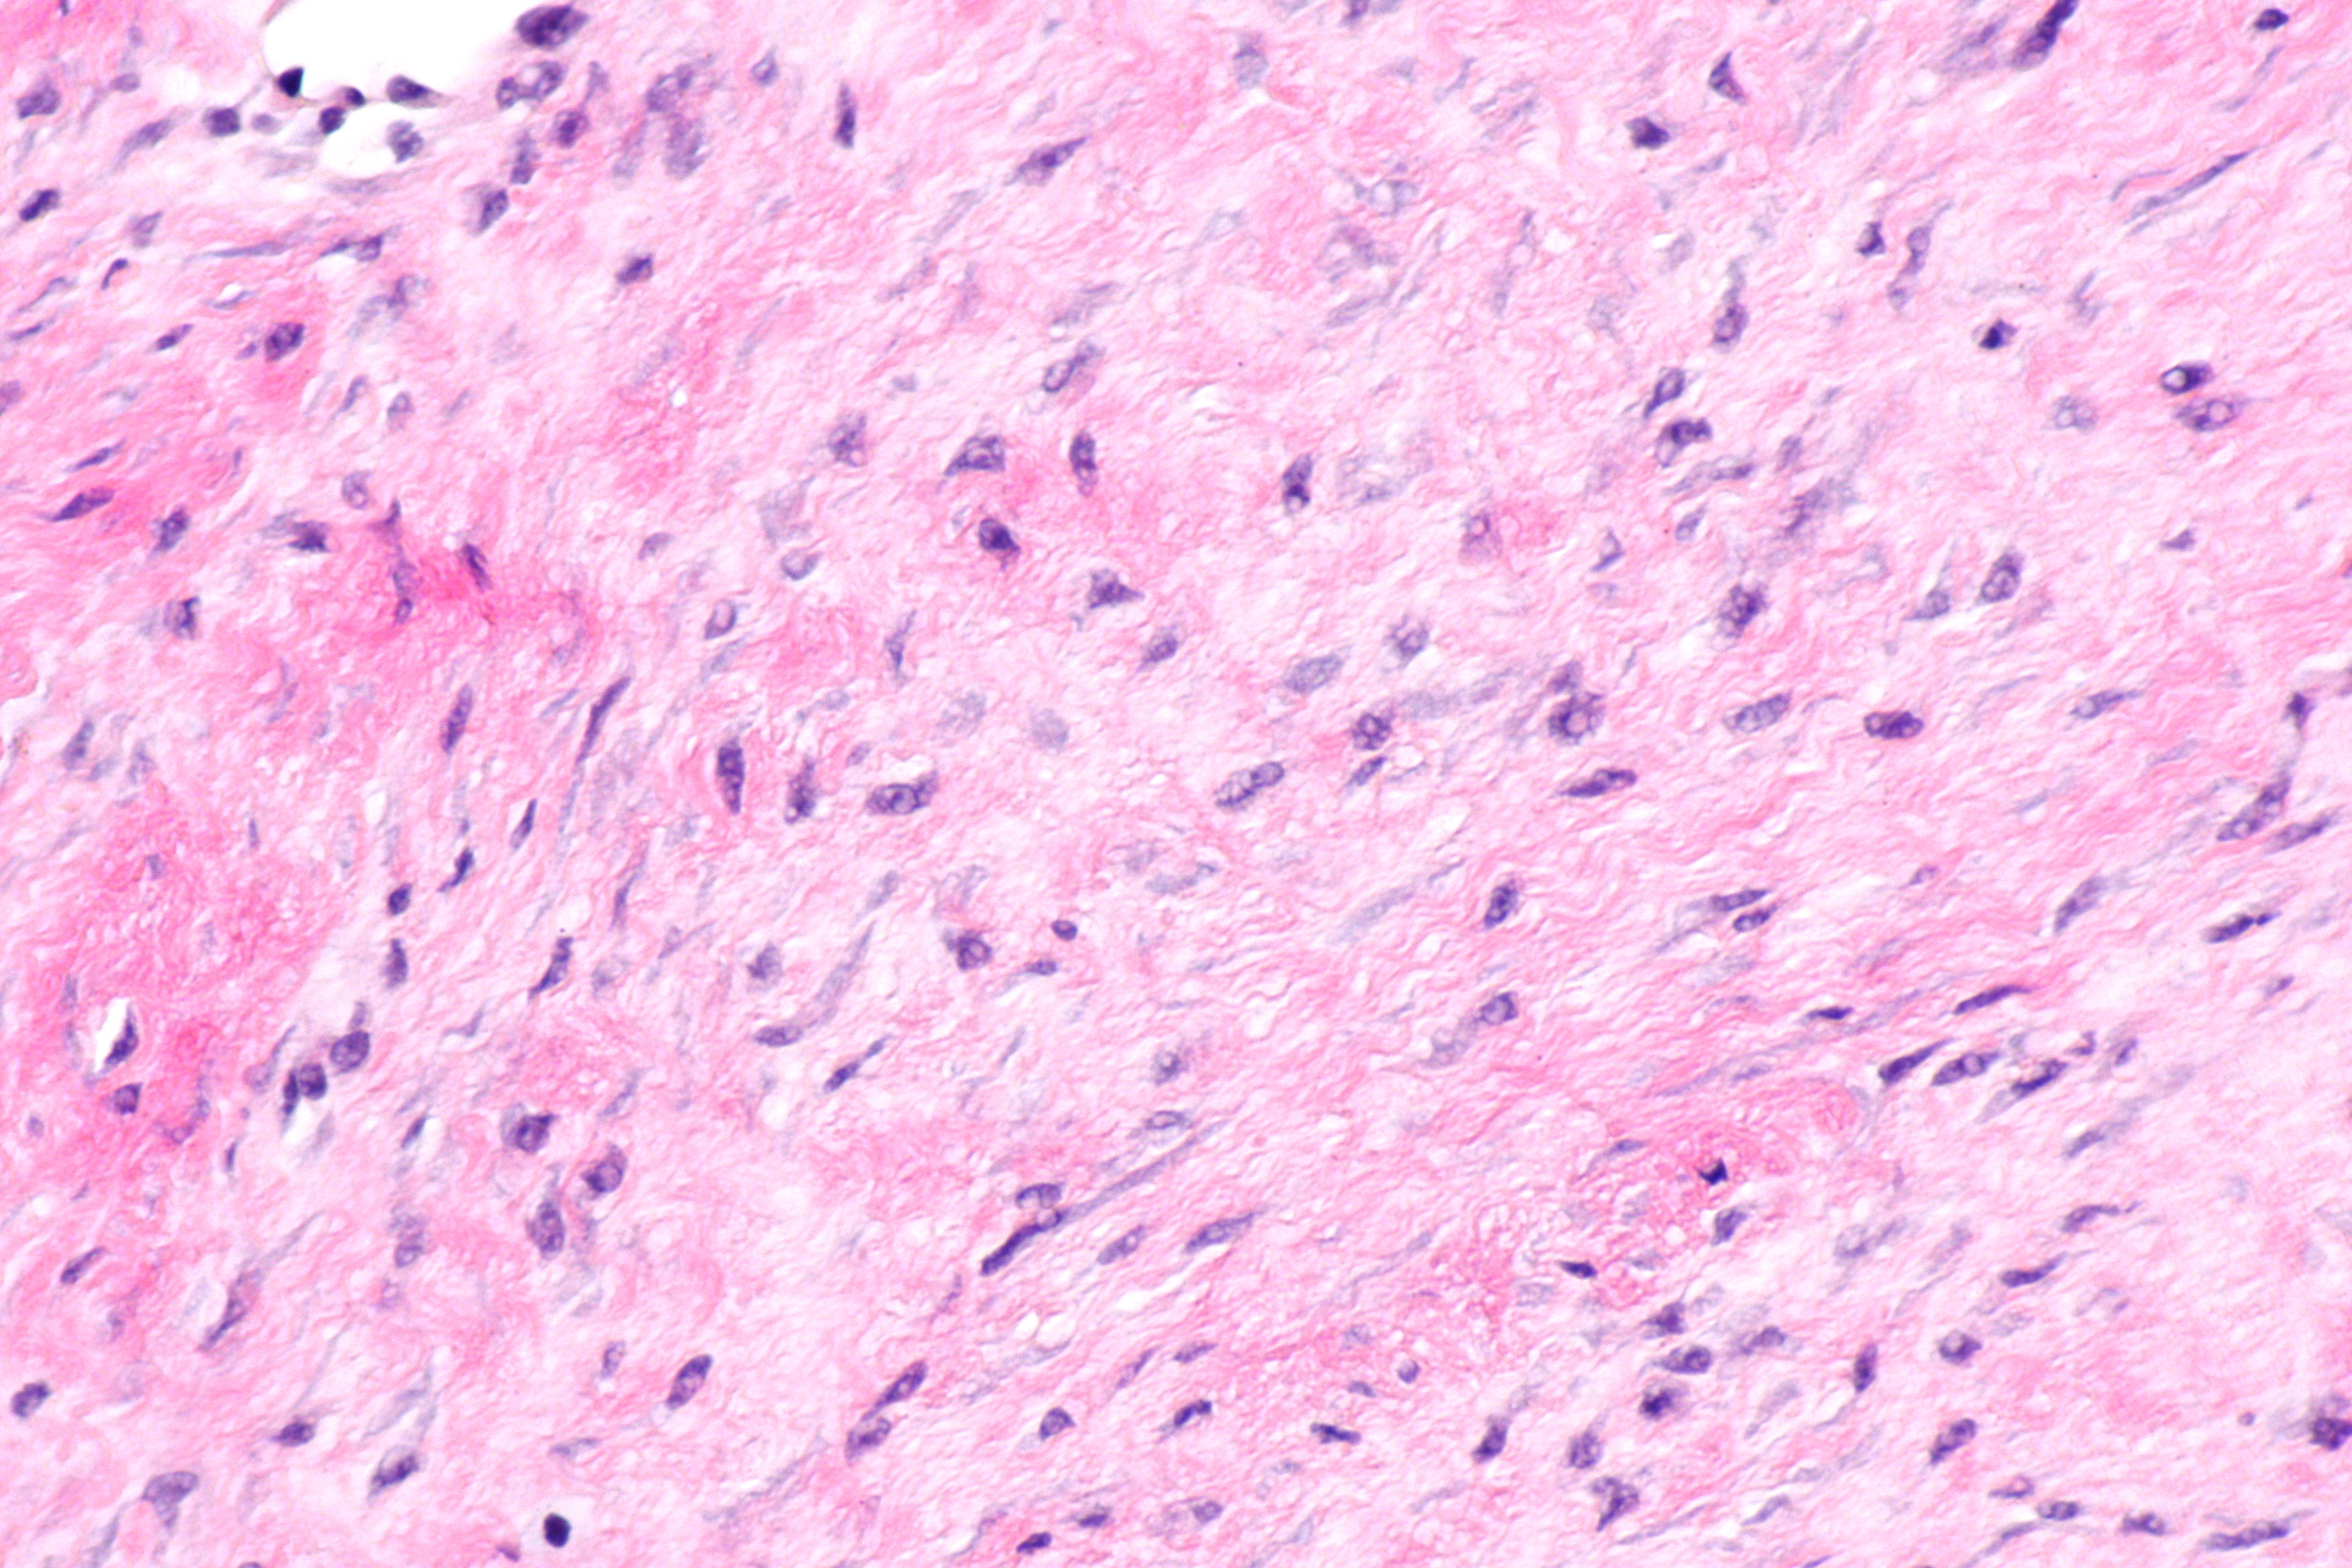

Histologic section of desmoid tumor tissue with spindle cells in fibrous connective tissue.

Desmoid tumors, also known as aggressive fibromatosis, are rare fibroblastic neoplasms that present a significant therapeutic challenge.1 Although benign and non-metastasizing, these tumors can behave aggressively at the local level, infiltrating surrounding structures and causing morbidity.2,3 Their variable clinical course, ranging from indolent stability to persistent progression, requires nuanced, individualized management.2,3